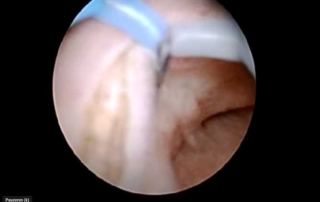

Cystoscopic resection of ureterocele

Information Author: M. Schettini The ureterocele is a cystic dilatation of the terminal ureter: its formation probably results from [...]